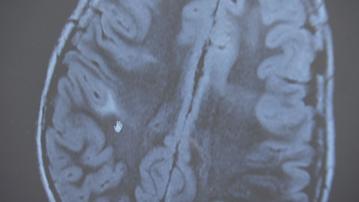

【Now新聞台】由世界衛生組織委託進行的最新調查發現,使用手提電話與患腦癌的風險並沒有關聯。

手提電話發展一日千里,成為現代人不可或缺的必需品。過去一直有人擔心,長期將手機貼近耳邊使用,會否增加患腦癌的風險。

一項由世衛委託進行的調查發現,兩者並沒有關聯。調查由來自澳洲等十個國家的十一名研究人員進行,涵蓋1994年至2022年的六十三份研究,評估手機應用、通訊基站、無線電發射器及職業關係的輻射暴露,會否增加成年人和兒童腦部、腦下垂體、唾液腺患癌及患上白血病的風險,調查亦有評估電視、嬰兒監視器、雷達等的射頻影響。

調查結果發現,即使手提電話和無線技術應用在過去二十年大幅上升,人類腦部和頭頸部位的癌症發病率並沒有相應增加,當中包括長時間打電話及使用手機超過十年的人,證明患上腦癌與使用手機並沒有確切關聯。至於接觸通訊基站及發射器,亦不會增加兒童罹患腦癌或白血病的風險。